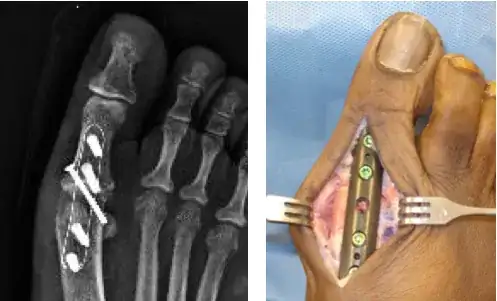

Metal, schmetal. Schmetal, I tell you! What are you, patching up Steve Austin? Carbon fiber is how one reinforces bones these days.

carbon fiber augmentation

https://www.podiatrytoday.com/exploring-carbon-fiber-fixation-lower-extremity

Carbon fiber technology provides strength and durability with ease of placement in comparison to stainless steel and titanium. The modulus of elasticity of the carbon fiber technology is closer to that of cortical bone than stainless steel or titanium implants, allowing the surrounding bone to function without undue stress from the internal fixation. The implants are composed of longitudinal and diagonally-oriented fibers of carbon, allowing for strength in multiple planes.

That xray is a little retro with the metal nails; those can be carbon fiber too. You don't need to shatter the bones. Slip the carbon fiber rod down the middle and sheathe the outside where you need it. The carbon fiber rod can flex like bone and if the bone breaks the rod will hold the pieces in place while your supersoldier chugs some of that Skelegro you did not need to use.

Carbon fiber rods and plates in bones is not fiction.